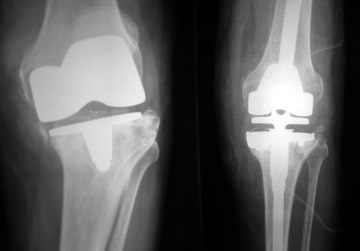

Revision Knee Replacement Surgery

What is a Revision Knee Replacement?

A revision knee replacement is an operation on a knee that has already had partial or total knee replacement surgery.  It is performed for a variety of reasons but frequently because a partial knee replacement needs to be converted to a total knee replacement.  The operation involves removing the implanted components and inserting new ones.